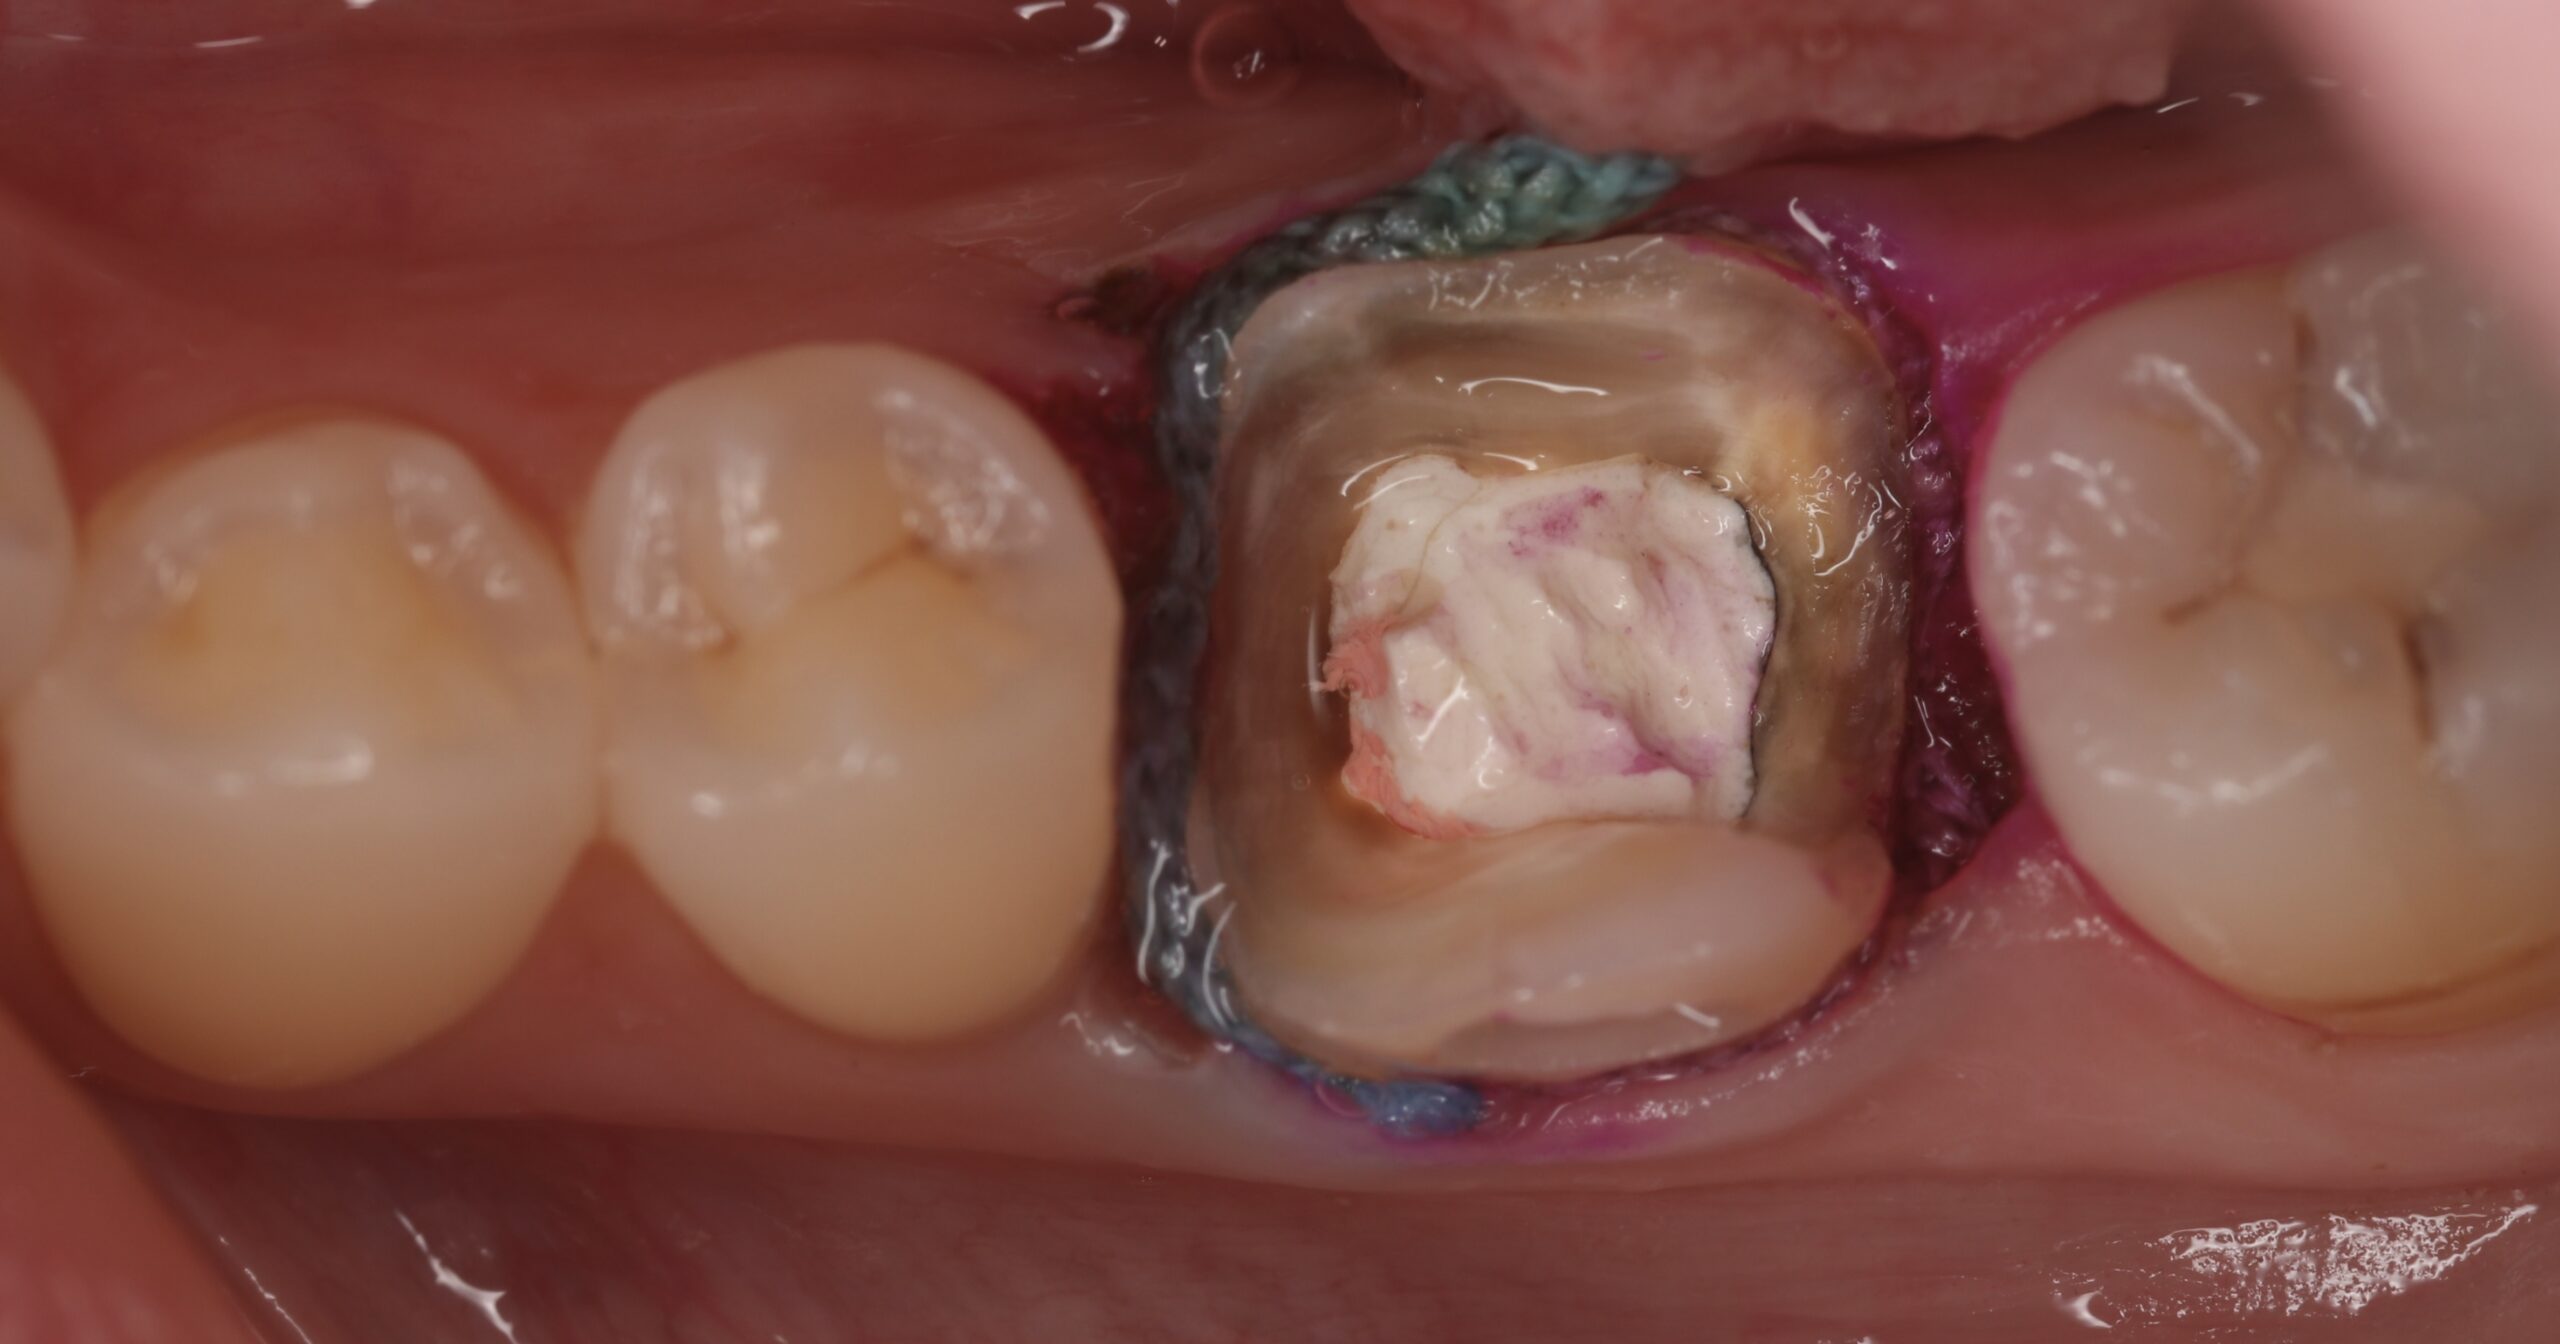

奥歯をジルコニアクラウンで治療した症例

BEFORE AFTER

| 主訴 | 噛むと痛い、銀歯のところを白く治したい |

| 治療内容 | 右下の奥歯の金属の被せものの周りからむし歯になっており、以前行われていた神経の治療(根管治療)を再度行った後、被せ物による修復を行いました。奥歯は噛む力が強くかかる部位であるため、高い強度を持つ「ジルコニアクラウン」を選択しました。金属を一切使用していないため、歯茎の黒ずみや金属アレルギーの心配がありません。 |

| 治療期間 | 約2ヶ月(根管治療期間含む) 通院回数:6回 |